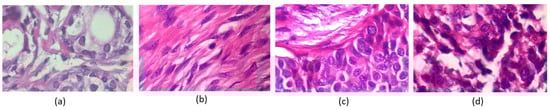

In contrast, uneven color distribution can occur when there are variations in the staining intensity of different regions in the tissue sample. Figure 2 shows various color distributions. For example, in some cancer tissues, certain areas may appear more intensely stained than others, indicating the presence of abnormal cells or tissues. Similarly, cell overlapping in histopathology images refers to the phenomenon where cells in the tissue sample appear on top of one another [6], making it difficult to distinguish individual cells. It can occur when cells have undergone abnormal changes, such as increased cell growth or decreased cell death, leading to tissue overcrowding. Cell overlapping can also be a sign of tissue invasion by cancer cells. All these characteristics of histopathology images can provide valuable information for diagnosis and prognosis.

Figure 2.

Breast cancer histopathology images from the BreakHis 400× image dataset. The images in (a,b) are classified as benign, and the images shown in (c,d) are classified as malignant by pathologists.